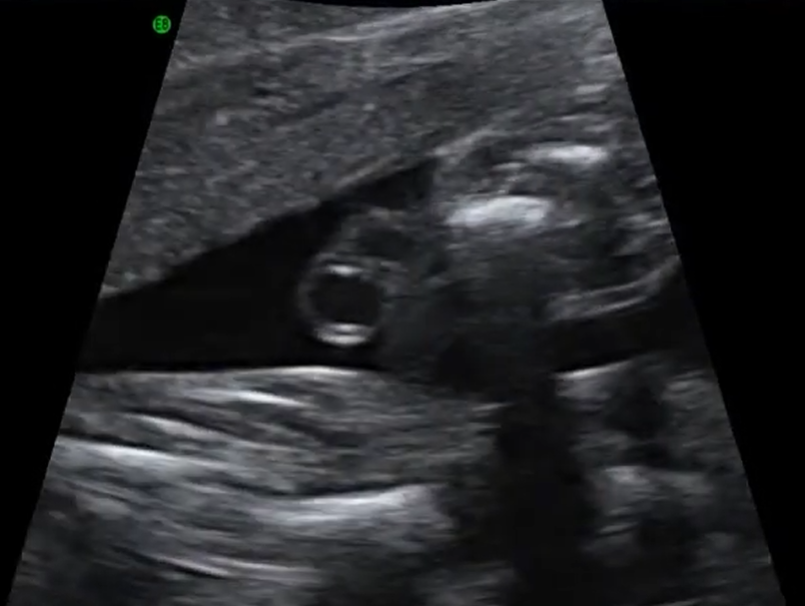

Nang dây rốn (Umbilical Cord Cysts)